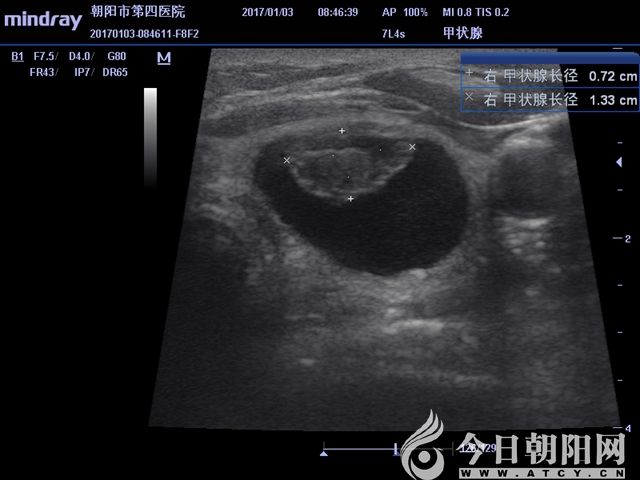

超聲測得實性結節(jié)大小

患者為65歲女性,發(fā)現(xiàn)左右側頸部包塊1個月,通過超聲檢查考慮甲狀腺腺瘤伴出血。患者從心理上不能接受頸部手術后切口瘢痕,拒絕手術切除,要求微創(chuàng)治療。針對患者要求,該院外科團隊為其設計了治療方案——行甲狀腺微波消融術。手術采用局麻,在超聲影像引導下,順利準確穿刺,抽出積血后,再于實性病變處用活檢針穿刺取病理,證實良性病變。